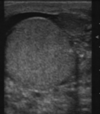

What is this imaging modality and what pathology is it showing

US testes

Green box= doppler effect

Blood flow less on RHS than LHS, right testicular enlargment

Testicular torsion